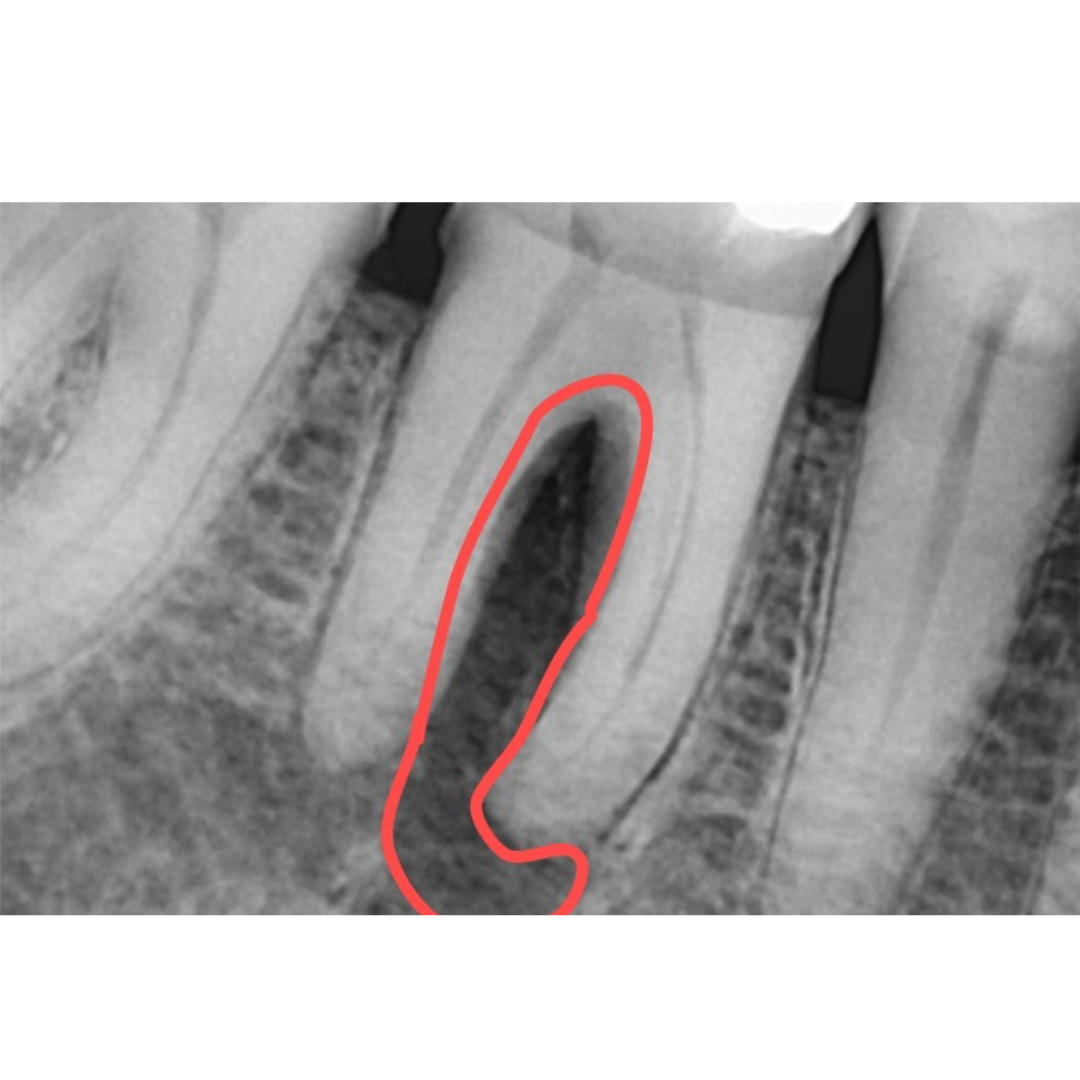

Saving Tooth with Help of Multi Speciality Approach

After

Before